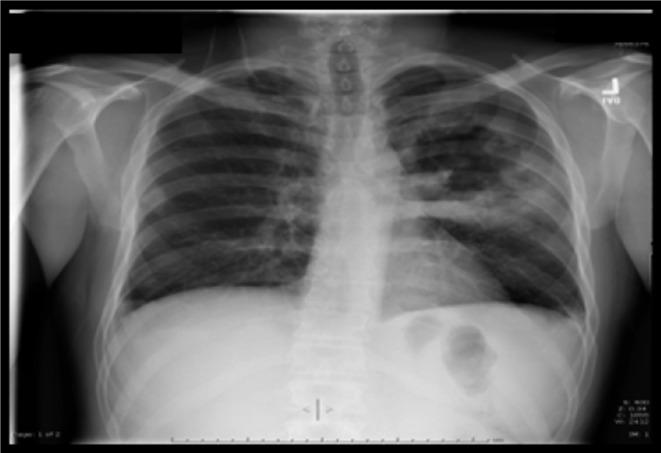

A 39-year-old male with newly diagnosed HIV had cavitary pneumonia initially attributed to Pneumocystis jirovecii but actually caused by Rhodococcus equi. After neurological deterioration, he was found to have intracerebral lesions caused by Toxoplasma gondii. This case underscores the inability to rely on the search for a unifying diagnosis (Ockham's Razor) in HIV-infected patients.

一名新诊断出感染艾滋病毒的39岁男性起初患有空洞性肺炎,最初认为是由耶氏肺孢子菌引起,但实际上是由马红球菌引起。在出现神经功能恶化后,发现他患有由刚地弓形虫引起的脑内病变。该病例强调了在艾滋病毒感染患者中不能依赖寻找统一诊断(奥卡姆剃刀原则)。